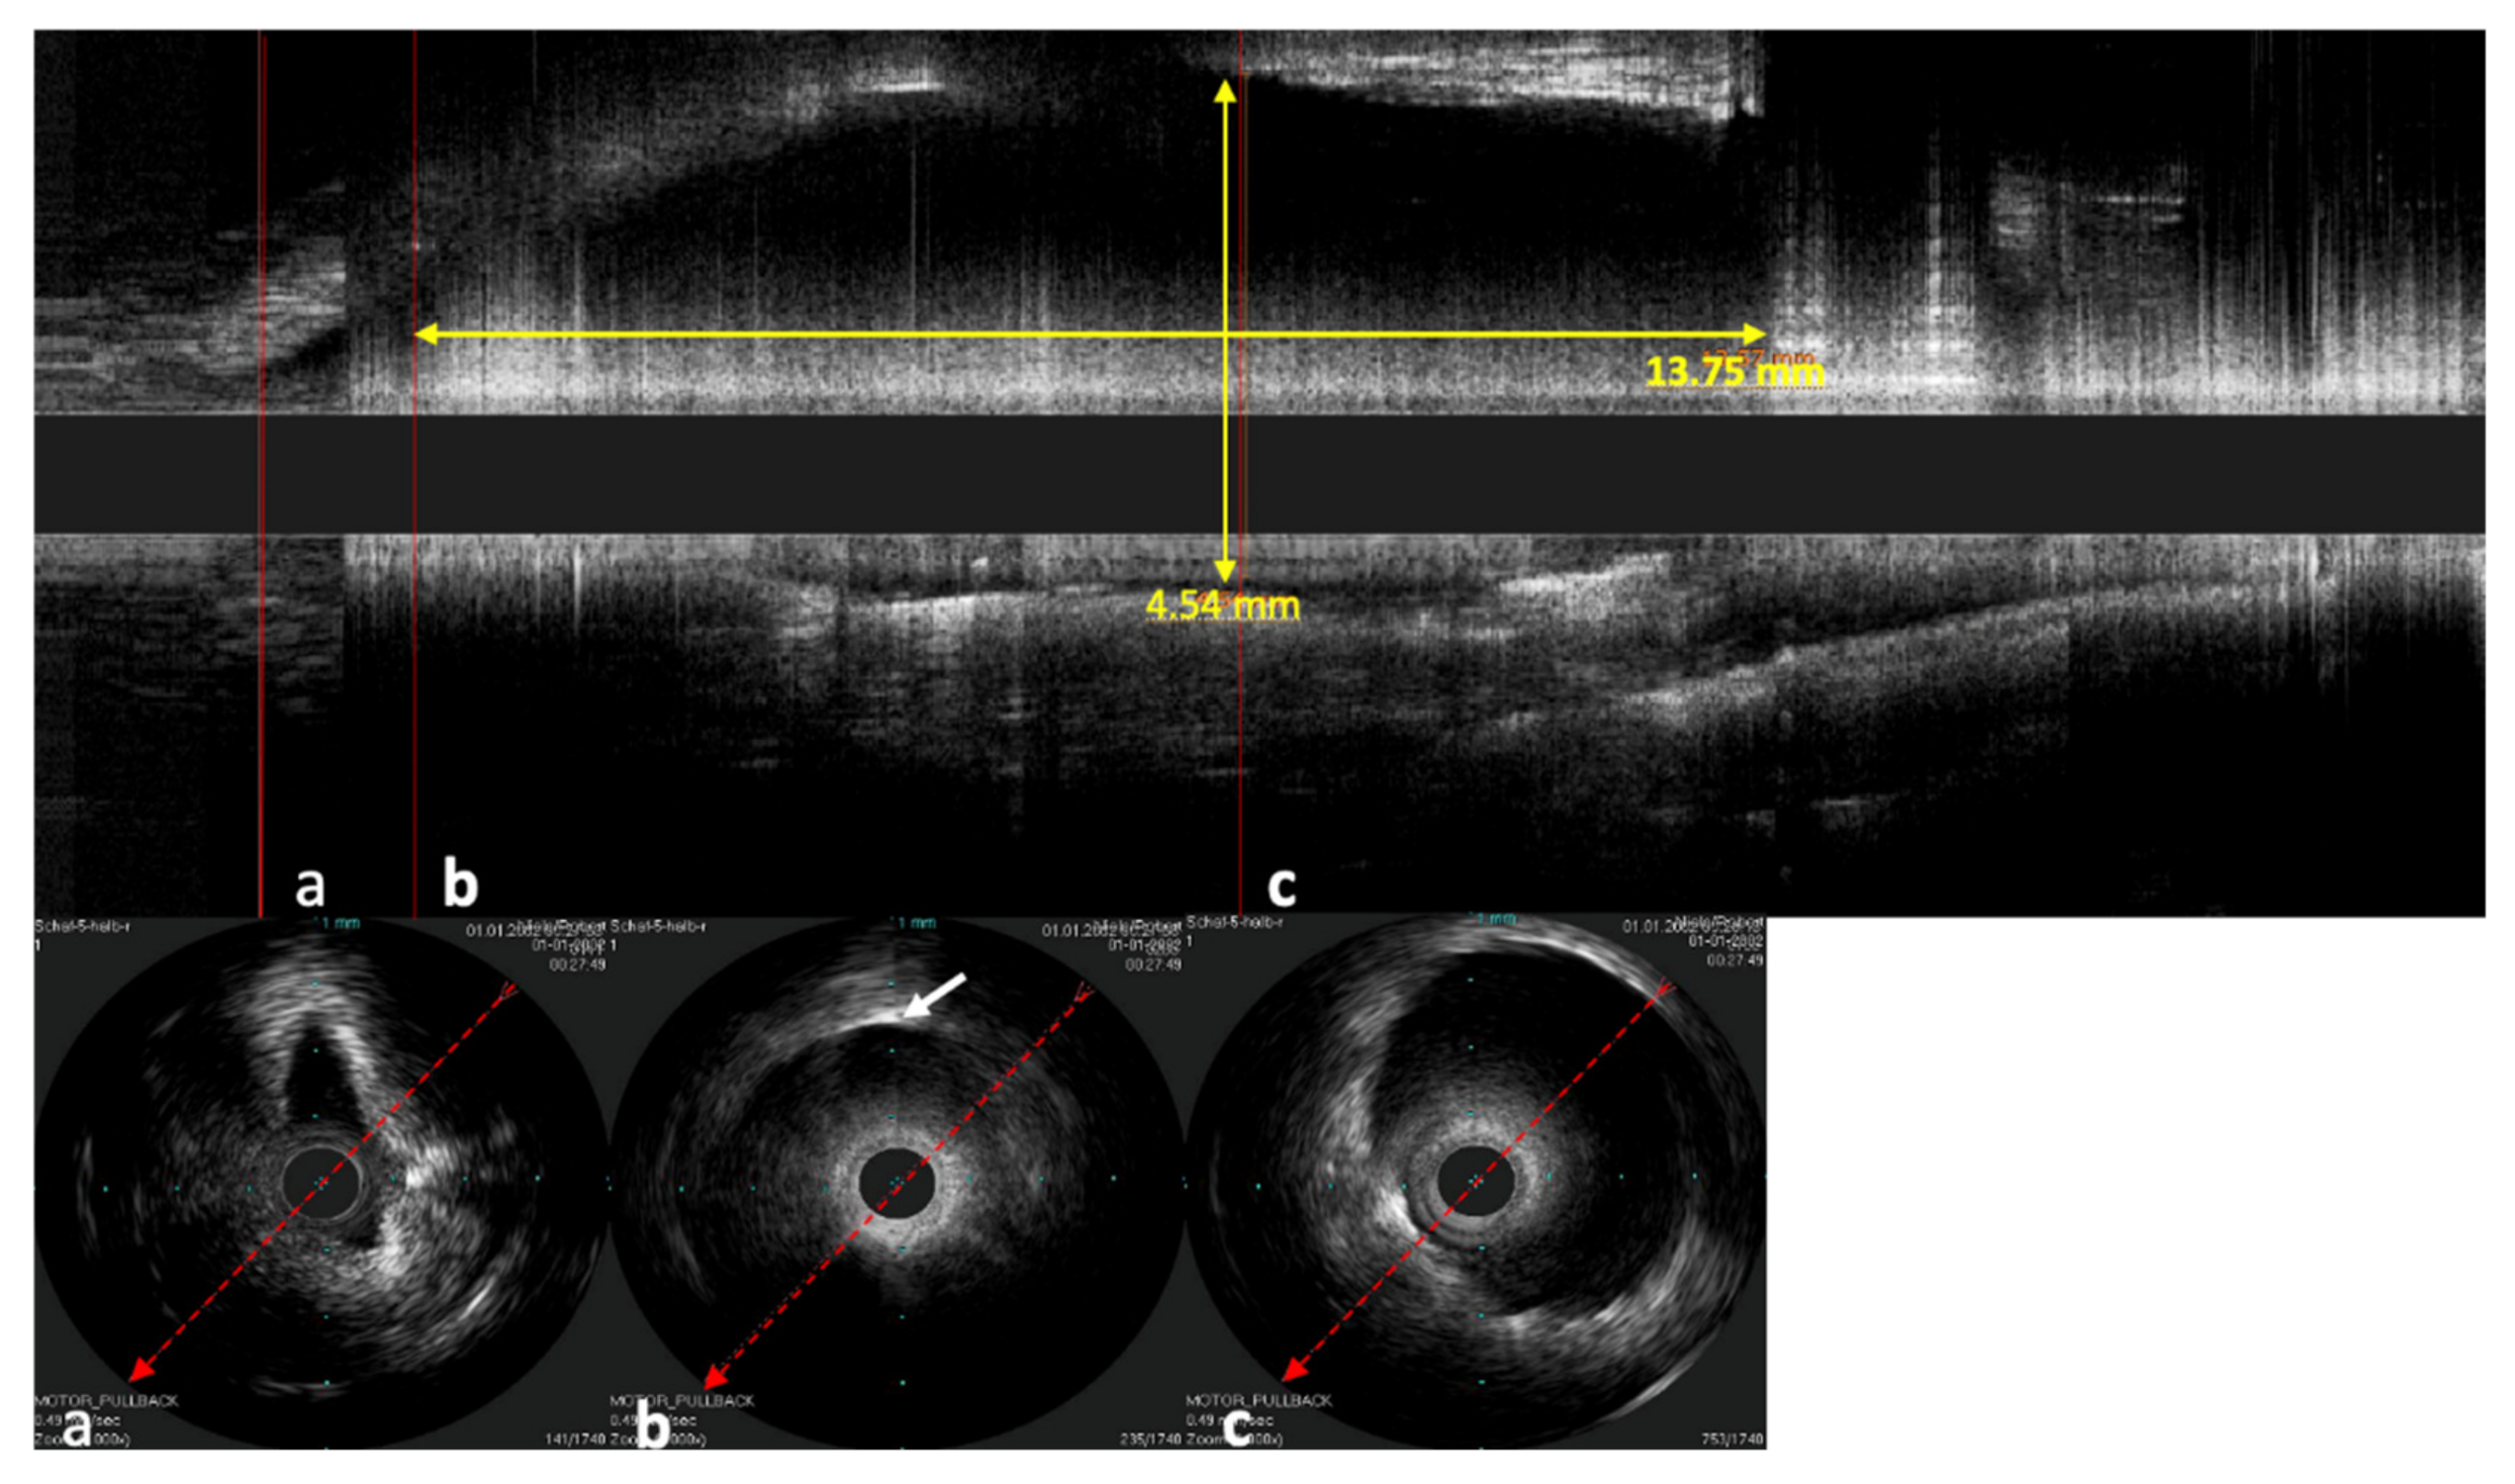

The stent inside of the ET was visualized by the echogenic metal struts of the stent and the widened lumen (Figure 7).

In the longitudinal view, not only can the stent shape be investigated but also how the mucosa of the ET lies around the stent and the position of the stent in the lumen of the ET (Figure 8). In one case, the catheter was next to the stent and not inside of the stent lumen. The stent struts were clearly visible next to the probe in the ultrasound image. Damage to the probe or the stent could not be detected in this case.

Figure 8. Sonographic image of the stented ET, performed with the Refinity ST probe. The upper image shows the longitudinal view of the scan. Parts (ac) show the respective cross-sections of the scans. Part (a) shows the area in front of the stent, where the tubal lumen widens toward the stent. Part (b) shows the initial area of the stent where the first stent strut can be seen sonographically (indicated by white arrow). Part (c) shows the cross-section in the middle section of the stent. The cross-section here was measured to be 4.54 mm. In the longitudinal view, a length of 13.57 mm was measured.